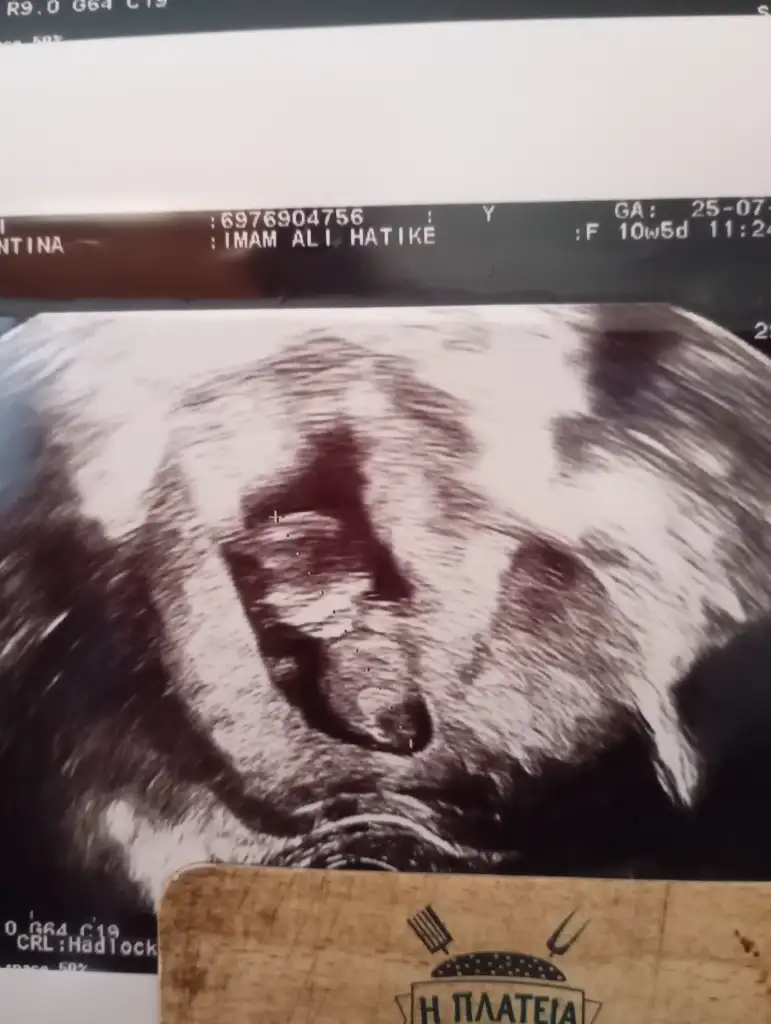

Banada tahminde bulunabilir misiniz? Kendi doktorum erkeğe benziyor başka bir doktor kıza benzettiği söyledi

• 1000106499.webp

1000106499.webp

30,7 KB · Görüntüleme: 51

• 1000106498.webp

1000106498.webp

23,3 KB · Görüntüleme: 52